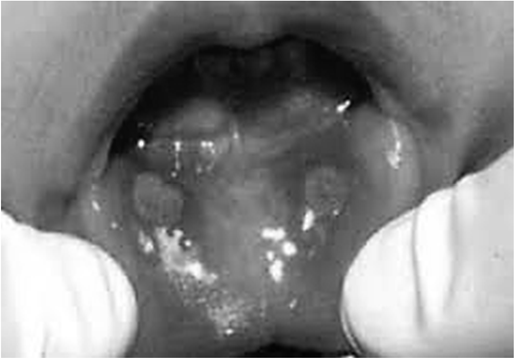

Uma paciente de 30 anos de idade reside em Vassouras (RJ) e queixa-se de febre, úlceras orais (imagem a seguir) e dor na região das mãos e dos pés há sete dias. Relata que teve aftas anteriormente, mas, dessa vez, estão maiores e mais dolorosas. Além das aftas, acha estranhas as manchas e a coceira no corpo. A paciente queixa-se também de emagrecimento, informando ter emagrecido 5 kg em três meses. Por causa do emagrecimento, foi submetida previamente a endoscopia digestiva alta (EDA), que diagnosticou gastrite e refluxo duodenogástrico. Inicialmente, foi tratada como estomatite viral e, atualmente, está em uso de nistatina associado a dexametasona, elixir para bochecho.

Tendo em vista esse caso clínico, a imagem apresentada e os conhecimentos médicos correlatos, julgue os itens a seguir.